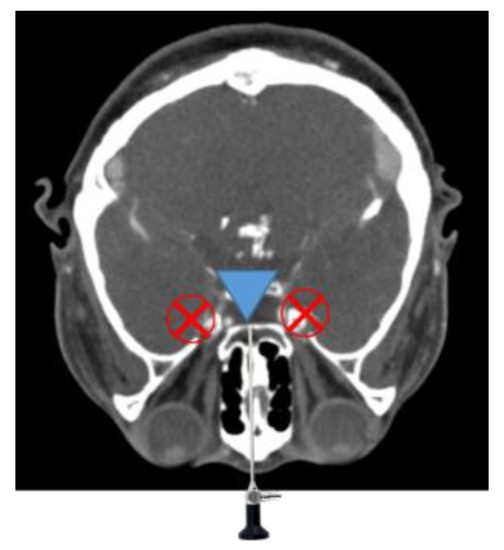

3.1. Proposed Surgical Navigation System

3.2. Registration for Construction of Navigation System